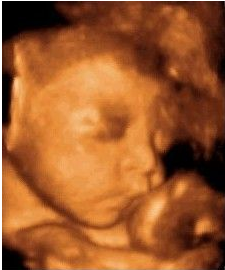

檢查室里面布置的很溫馨,醫(yī)生微笑著接待了我,讓我躺在軟軟的檢查床上,接下來就是期待已久的時(shí)刻了,醫(yī)生先在我肚子上抹了種滑溜溜的東西,然后用掃描儀在肚皮上滾來滾去,奇跡出現(xiàn)啦!屏幕上出現(xiàn)了小寶寶的影像,瞬間覺得奇妙又幸福。出乎我的意料的是畫面十分清晰,不用醫(yī)生解說,我這個(gè)門外漢也可以看清楚寶寶的樣子,醫(yī)生說這是從美囯引進(jìn)的ge四維彩超,能夠多角度、全方位的觀察到腹中寶寶的狀態(tài)。

可是寶寶似乎不怎么配合我們,舉著小手擋在臉前,還留給了我們一個(gè)美麗的側(cè)臉,這是猶抱琵琶半遮面的節(jié)奏么?看來我家小寶貝兒是個(gè)害羞的娃呀。我跟寶寶輕輕說著話,叫它乖寶寶,可是寶寶還是一副我不理你的樣子,這時(shí)醫(yī)生用手輕輕捏了下我的肚子,寶寶這才把臉轉(zhuǎn)了過來,我終于看到寶寶的正面了,簡直是和它媽媽一樣美呆了,嘻嘻。

醫(yī)生一邊給醫(yī)生助理報(bào)數(shù)據(jù),一邊耐心的為我講解,哪里是寶寶的手啊腳啊,之后我們又聽到了臍血流和胎心音,醫(yī)生說寶寶的身體很健康,一切都正常,我這才放心下來。整個(gè)四維彩超檢查過程大約持續(xù)1個(gè)小時(shí),可我仍覺得意猶未盡,期間還把寶寶的萌照拍了下來,是不是很可愛呢?